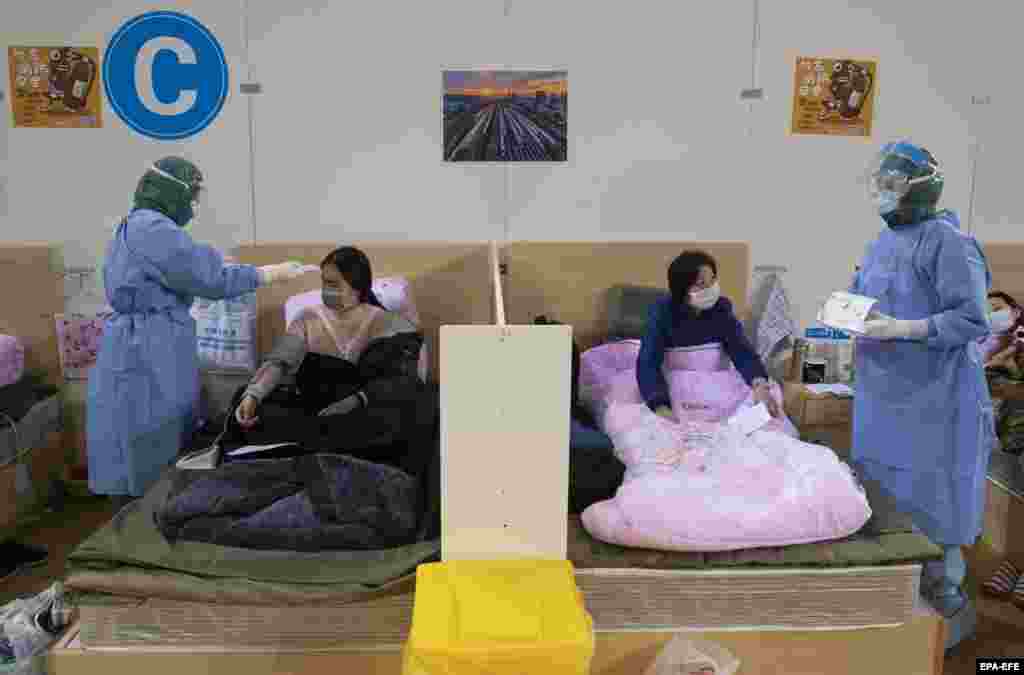

Опыт Китая, Италии, Испании, Франции и США показал, что медицинские учреждения могут «захлебнуться» от тысяч пациентов, нуждающихся в неотложной медицинской помощи. О тех мерах, на которые пришлось пойти правительствам разных стран в ожидании потока больных, рассказываем в фоторепортаже.

Опыт Китая, Италии, Испании, Франции и США показал, что медицинские учреждения могут «захлебнуться» от тысяч пациентов, нуждающихся в неотложной медицинской помощи. О тех мерах, на которые пришлось пойти правительствам разных стран в ожидании потока больных, рассказываем в фоторепортаже.